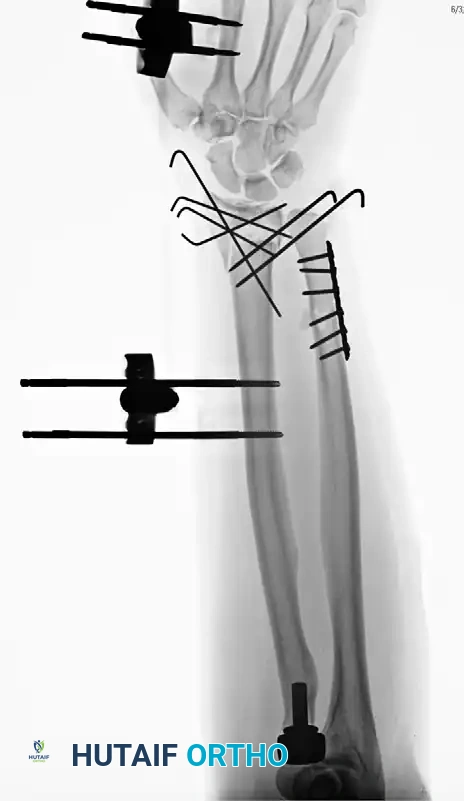

Case Example: Essex-Lopresti Reconstruction

The following sequence demonstrates the complex management of an Essex-Lopresti injury complicated by radial shortening.

Figure 57-80A: Initial presentation showing radial head fracture and longitudinal instability.

Figure 57-80B: Associated DRUJ disruption and ulnar variance.

Figure 57-80C: Attempted initial stabilization.

Figure 57-80D: Progressive proximal migration of the radius due to unrecognized or inadequately treated IOM disruption.

Figure 57-80E: Application of an external fixator; however, profound radial shortening and ulnocarpal impaction remain evident.

Figure 57-80F: Definitive revision surgery utilizing a radial head prosthesis to restore the proximal buttress and reestablish anatomical radial length.